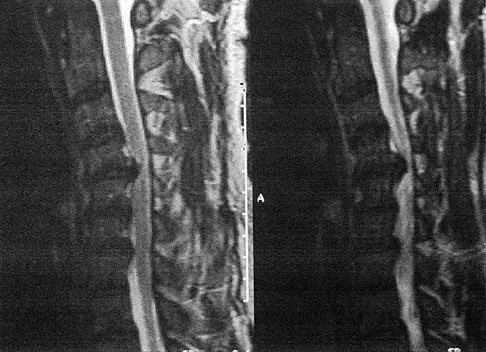

A healthy 16-year-old boy has had increasing pain in the right knee for the past 3 months. Examination reveals warmth and swelling around the distal femur. Radiographs and an MRI scan are shown in Figures 51a through 51c, and a biopsy specimen is shown in Figure 51d. What is the most likely diagnosis?

Explanation